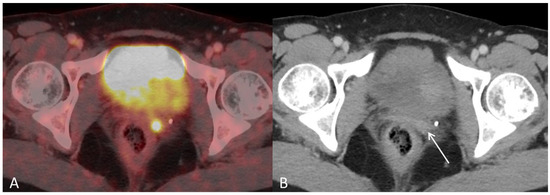

Figure 3. (A) Baseline axial PET/CT fused and (B) axial CT shows a small metabolic active hyperdense tumour located in the left vaginal corner, verified by biopsy as representing a metastasis from endometrial hepatoid adenocarcinoma ((B), arrow).

Figure 4. (A) Baseline axial PET/CT fused and (B) axial CT shows several non-enlarged retroperitoneal lymph nodes with high metabolic activity ((A,B), arrows). The lymph nodes were not suspicious for malignancy on CT alone.